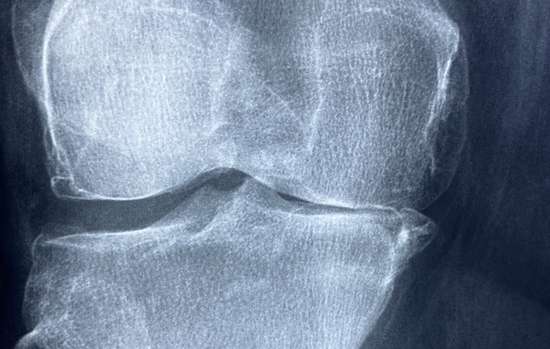

Названы вредные привычки, убивающие суставы и кости